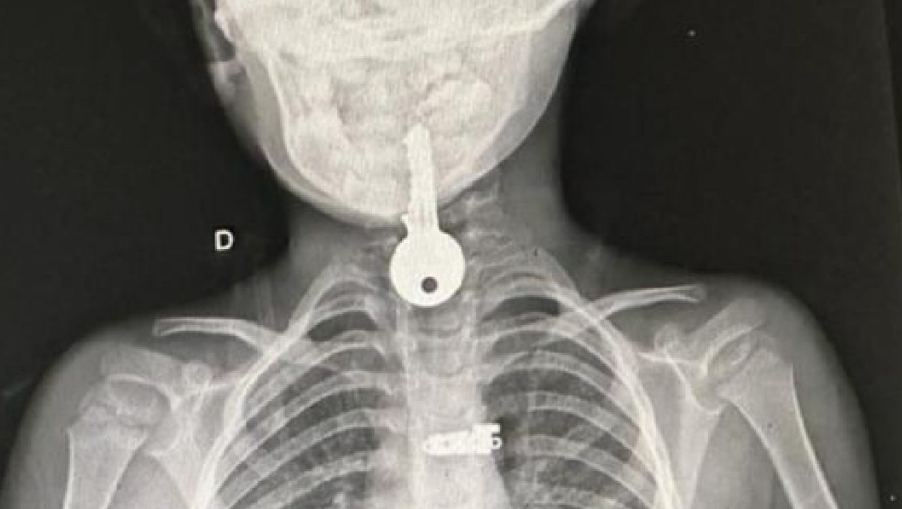

A chave ficou presa no esôfago da criança- Foto: Reprodução

Uma criança de apenas 4 anos engoliu uma chave, na última segunda-feira (6), em Porto Walter. Diante da emergência, ele teve que ser encaminhado por meio do Tratamento Fora de Domicpilio (TFD) ao Hospital do Juruá, para retirada do objeto, que ficou preso em seu esôfago.

Ao chegar ao Hospital de Cruzeiro do Sul, a criança foi atendida por especialistas e teve o objeto retirado de seu esôfago. Seu estado de saúde é considerado bom deverá ser liberado em breve para retornar a seu município de origem.